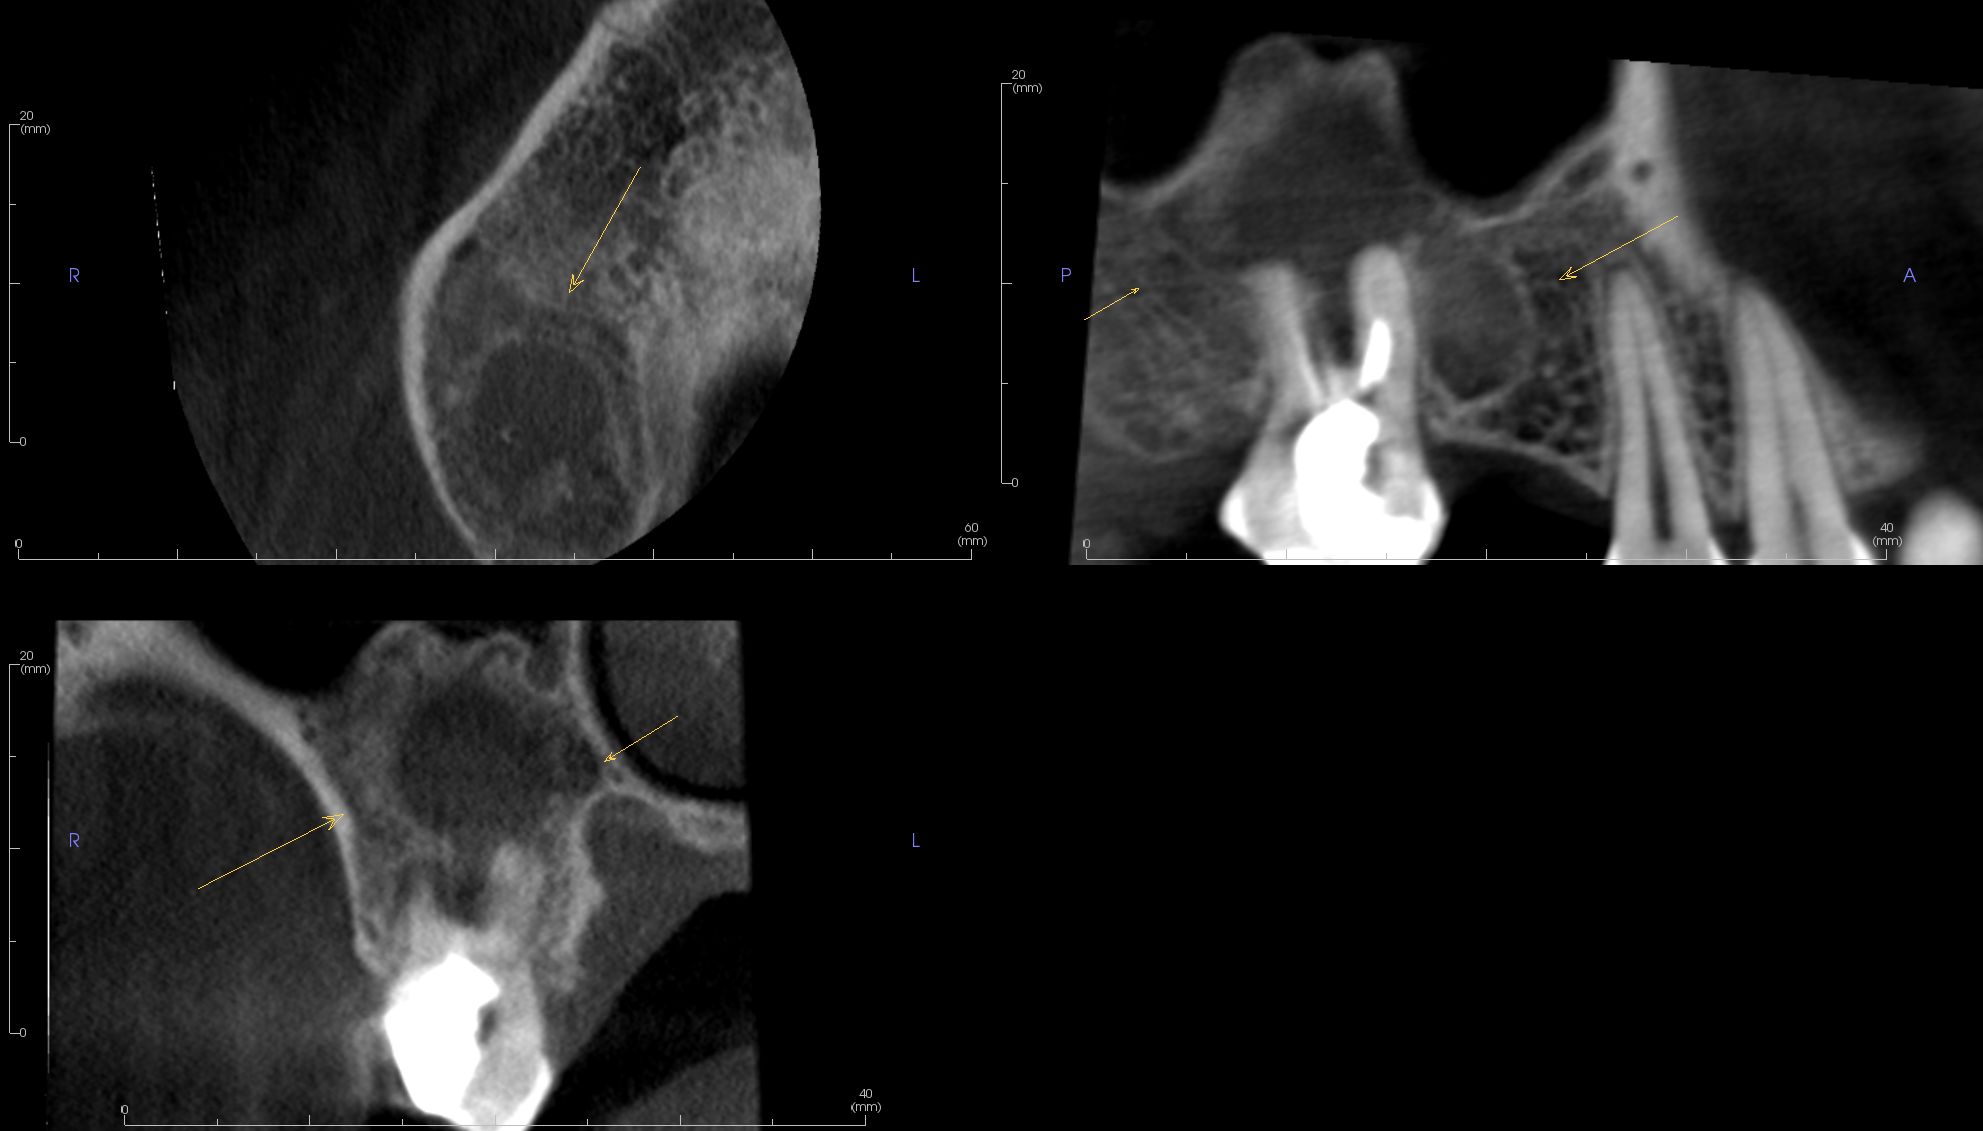

Image Portfolios visually communicate the imaging goals to you and your patient.